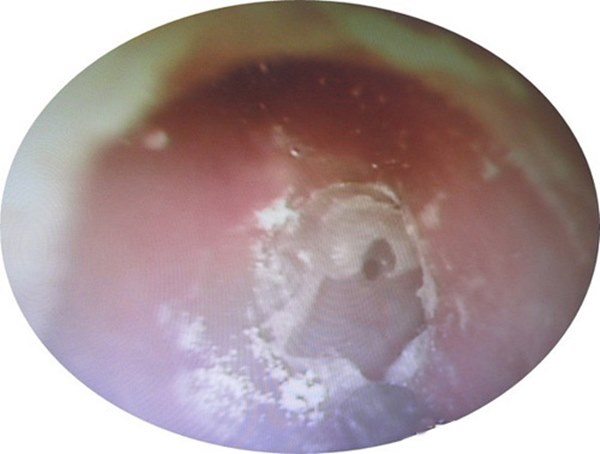

Bệnh nhân chia sẻ, bà có thói quen dùng tăm bông ngoáy tai hàng ngày. Bác sĩ Li Ruiwen chỉ định nội soi tai và kết quả cho thấy trong tai của người bệnh phủ đầy nấm mốc trắng như bông tuyết.

Bác sĩ Li tiến hành lau sạch phần nấm mốc và đã bị sốc khi thấy còn lớp mủ dày phía bên trong và màng nhĩ đã xuất hiện lỗ thủng. Sau 2 tháng điều trị bằng kháng sinh và thuốc chống nấm, tình trạng của bệnh nhân đã được cải thiện rõ rệt.

Lỗ thủng màng nhĩ ở tai bệnh nhân 56 tuổi